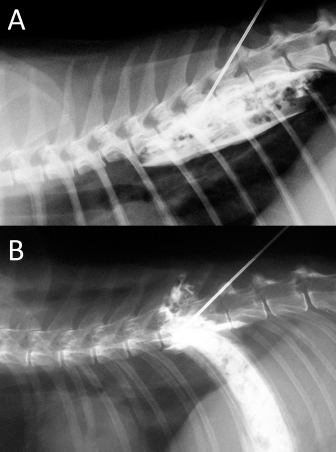

Fig. 6. NMB and ioversol mixed longitudinal and cloud-like (A) and intercostal (B) spread pattern in a lateral radiograph of a dog cadaver.

Although with some minor intra- and inter-specific differences, a positive air-LOR test was associated with longitudinal spread along the extrapleural compartment of the TPVS in 100% of the animals. In dog cadavers, the median injected volume (ml kg−1) of the mixture was 0.6 ml (0.22–1.25). The lateral thoracic radiographs showed multi-segmental spread in 100% of the subjects, with a median of 4.5 (2–10) vertebrae and a distribution of 2.5 (0–7) vertebra cranial and 1.0 (0–3) vertebra caudal to the injection level. A longitudinal spread pattern was noted on all radiographs, mixed with a cloudy pattern in 11/14 (78%) images and with an intercostal pattern at the level of the ninth intercostal space in 1/14 (7%) image (Fig. 6). Necropsy revealed multi-segmental ipsilateral longitudinal spread in 100% of the subjects (Fig. 7). The median stained intercostal spaces were 6.5 (4–11), with 5 or more spaces stained in 78%, whereas contralateral longitudinal spread was detected in 9/14 (64.3%) spaces, with a median of 2.5 (0–6) (Fig. 8). The median cranial versus caudal spread ipsilateral and contralateral to the injection site was 3 (1–7) versus 2 (0–3) and 0 (0–4) versus 1 (0–2) space, respectively. Distributions of NMB and ioversol after each mixture injection are shown in Figure 9. The only statistically significant correlation was between the radiographical and the necroscopic assessment of the longitudinal spread in the dog cadavers ( p=0.0028).

In cat cadavers, the median injected volume (ml kg−1) was 0.84 ml (0.6–1.5). The lateral thoracic radiographs disclosed multi-segmental spread in all of the subjects, with a median of 5 (2–6) vertebrae and distribution of 2 (0–3) vertebrae cranial and 2 (1–2) vertebrae caudal to the injection level. A mix of cloudy and linear spread patterns was noted on all radiographs, with the concurrent presence of an intercostal pattern at the level of the ninth intercostal space in 1/6 (17%) image (Fig. 10). Necropsy revealed multi-segmental ipsilateral longitudinal spread in 100% of the subjects. The median number of stained intercostal spaces (dorsal aspect) was 6.5 (5–7), with 5 or more spaces stained in all subjects, whereas contralateral longitudinal spread was seen in 5/6 (83.3%) subjects, with a median of 5 (0–7) (Fig. 11). The median distribution of the cranial vs. caudal spread ipsilateral and contralateral to the injection site was 3 (2–4) versus 2.5 (1–3) spaces and 2 (0–4) versus 2 (0–3) spaces, respectively. Staining of the parietal pleura surrounding the dorsal mediastinum, the so called pre-vertebral space and the proximal intercostal spaces were observed in all subjects, regardless of the volume or the spread pattern. Distributions of NMB and ioversol after each mixture injection are shown in Figure 12.